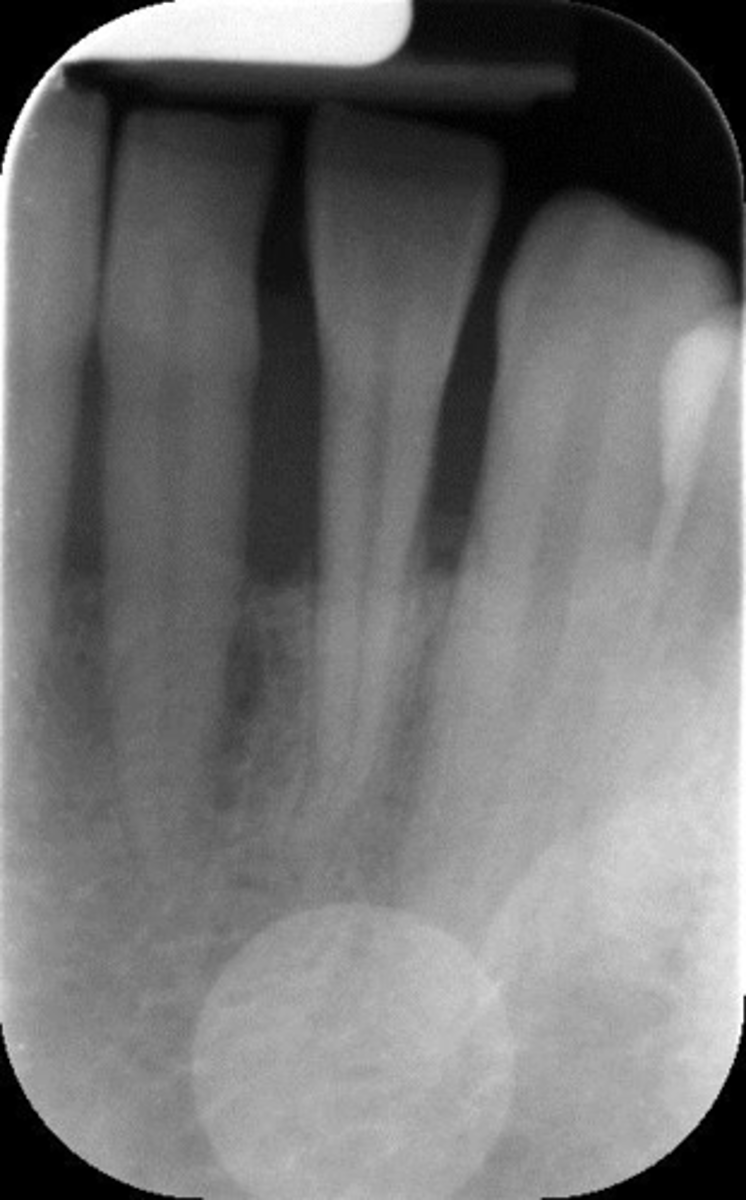

Damage, elongation, can't see apices

What is this error?

Horizontal angulation, no apices show, vertical angulation